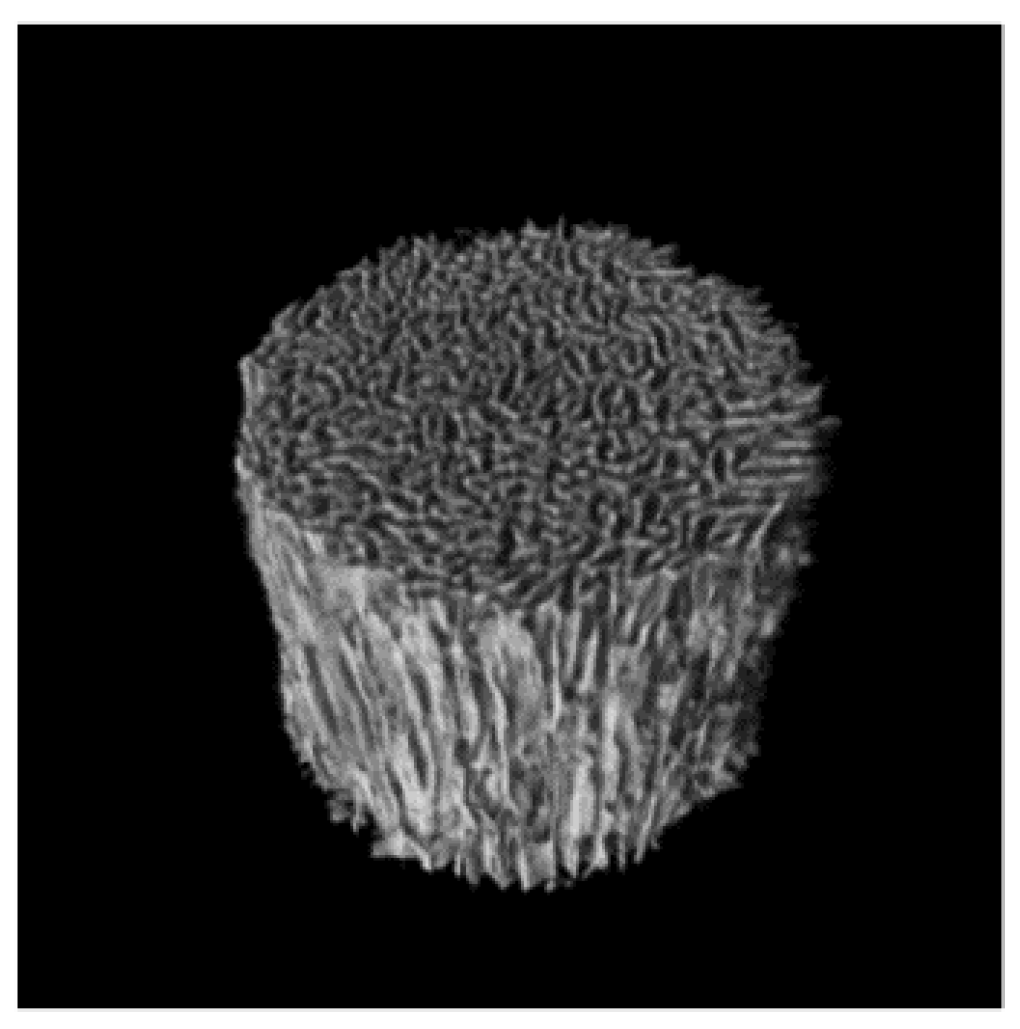

3.1. Bone Defect Animal Model